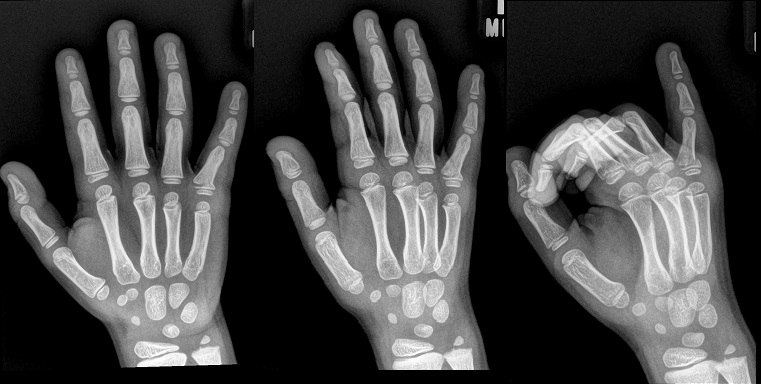

An 80 year old female presents to your office with a left ring finger deformity after a fall one week ago. She initially went to urgent care and xrays were unremarkable for a fracture (Figures 1 and 2). A photo of her left ring finger is shown in figure 3. On physical exam the left ring finger is in hyperextension at the PIP joint and flexion at the DIP joint. She able to flex her PIP joint with full motion. What is the best treatment option?